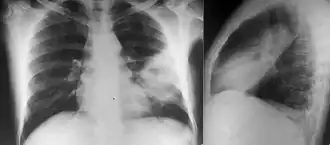

Imaging

Various imaging modalities can also help with the diagnosis of melioidosis. In acute melioidosis with the spreading of the bacteria through the bloodstream, the chest X-ray shows multifocal nodular lesions. It may also show merging nodules or cavitations. For those with acute melioidosis without the spread to the bloodstream, chest x-ray most commonly shows upper lobe consolidation or cavitations.[9] In chronic melioidosis, the slowly progressing of upper lobe consolidation of the lungs resembles tuberculosis.[9] For abscesses located in other parts of the body apart from the lungs, especially in the liver and spleen, CT scan has higher sensitivity when compared with an ultrasound scan. In liver and splenic abscesses, an ultrasound scan shows "target-like" lesions while CT scan shows "honeycomb sign" (abscess with loculations separated by thin septa) in liver abscesses.[9] For melioidosis involving the brain, MRI have higher sensitivity than a CT scan in diagnosing the lesion. MRI shows ring-enhancing lesions for brain melioidosis.[9]